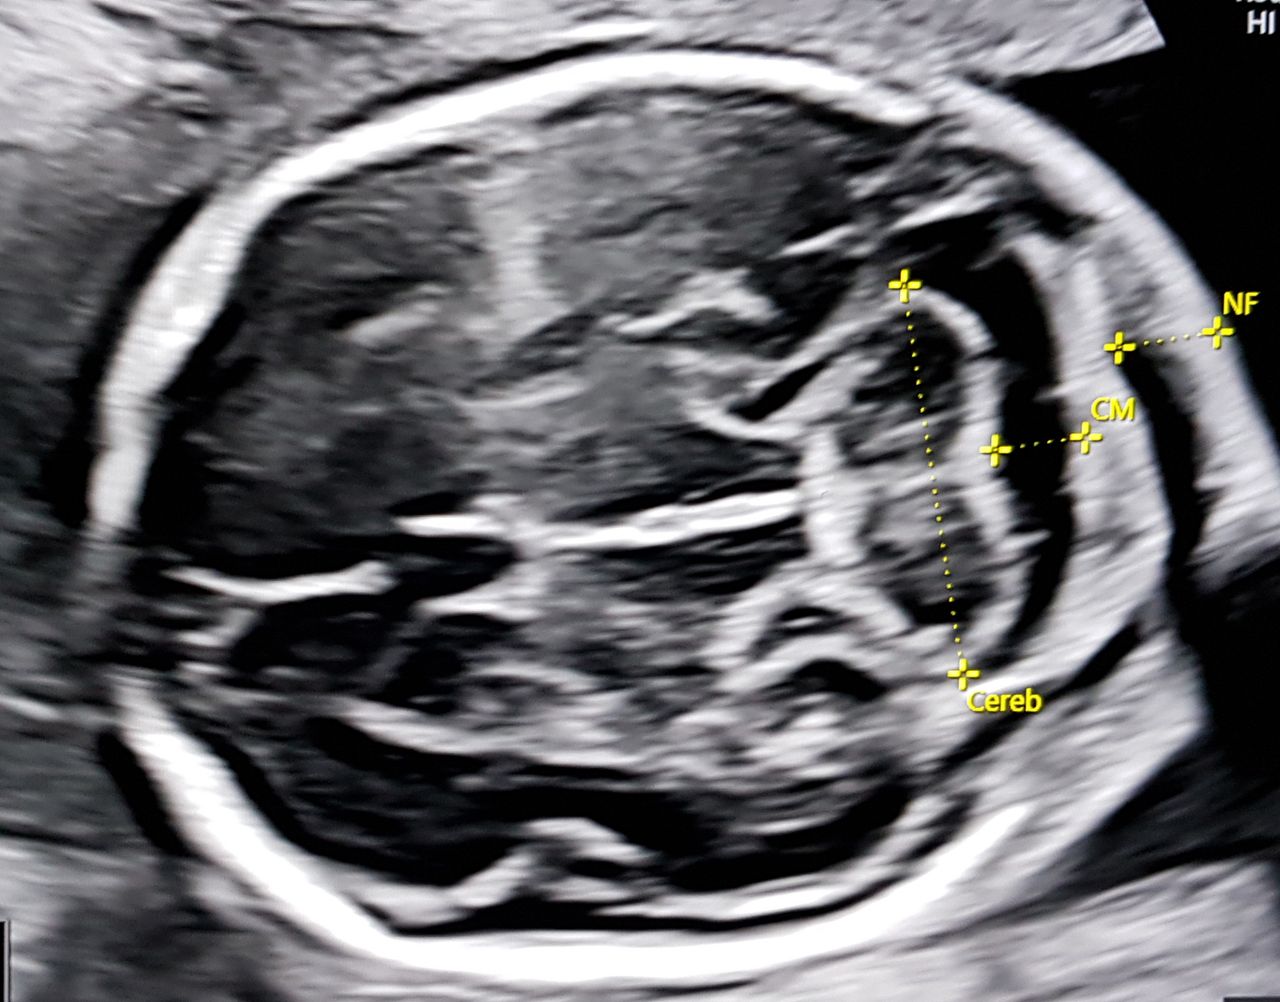

4- Nadia Fichera 1, Vito Leanza 1, Morena Maria Monteleone 1, Giuliana Chiara Maugeri 1, Gianluca Leanza 2, Antonio Carbonaro 1, Salvatore Carbonaro 3, Maria Giovanna Verzì 1, Marco Antonio Palumbo 1 Corpus callosum agenesis: prenatal diagnosis and neurodevelopmental outcome. European Gynecology and Obstetrics. 2020; 2(4):205-209

Foto e video